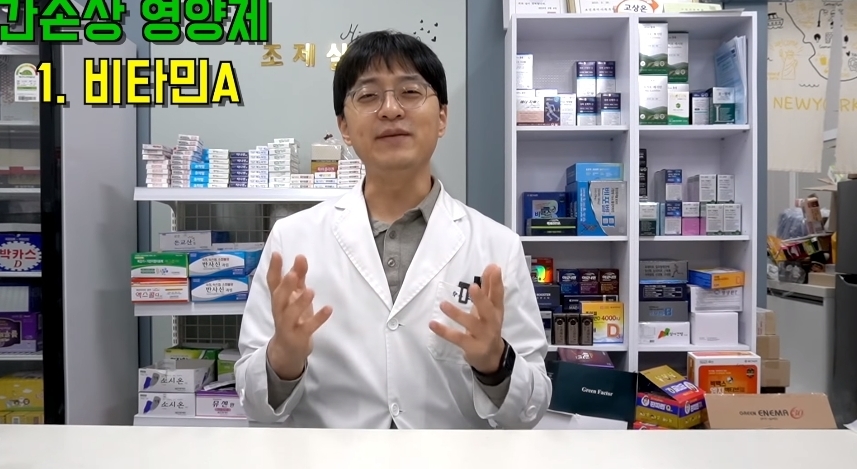

다음은 해당 게시물에 올라온 내용이다.

해당 게시물에는 먹으면 오히려 몸에 안좋은 영양제들이 올라왔다.